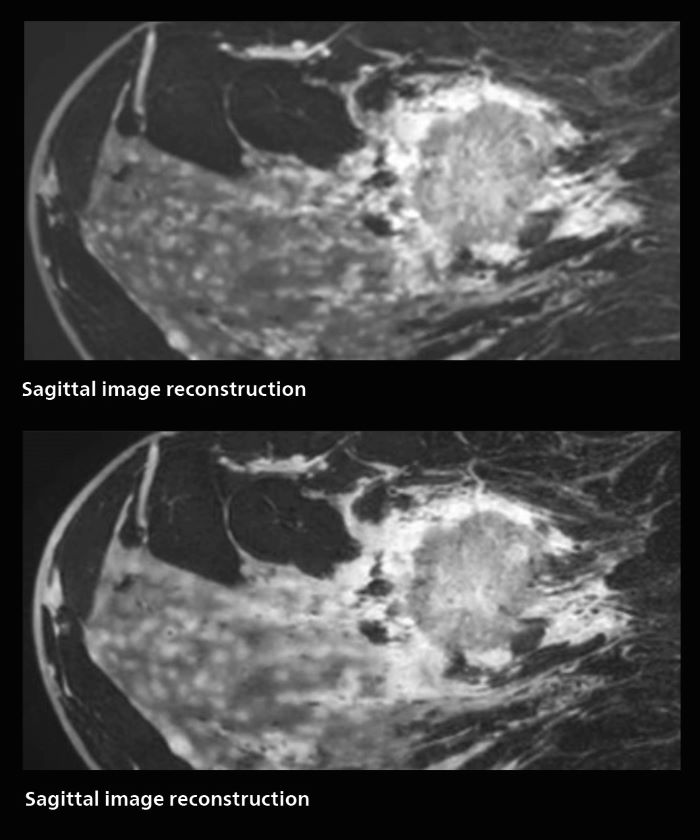

3D MRI of breast cancer

Scanning was performed with two different voxel sizes. AI enabled volume MRI allows image reconstruction in other directions. Biopsy revealed invasive ductal carcinoma in this patient. Performed on Elition X.

Fast AI-enabled MRI of breast cancer: comparing 3D acquisitions with 0.75 mm and 0.6 mm isotropic voxels.

Speed and high image quality are also important factors determining the diagnostic value of breast MRI. “When the spatial resolution is not high enough for making the diagnosis of breast cancer, a very difficult decision must be made,” says Dr. Katahira. “Since SmartSpeed now allows us to increase the resolution, we can often easily provide a confident answer. In the past with SENSE we used 1.2 mm isotropic voxels in breast imaging after contrast admission. With Compressed SENSE that is 0.8 mm. Now with SmartSpeed we can acquire 0.6 mm isotropic voxels and the images are so clear that even tiny details are clearly visible.”

“For example, we can now scan 20 consecutive, very fast dynamic images of the mammary glands with a single 3-second volume acquisition. This allows us to see how the blood flow is progressing in a very different way.”

“The use of SmartSpeed has considerably improved our breast cancer imaging, with higher temporal resolution, higher spatial resolution, and higher SNR compared to the past, when we were using just Compressed SENSE. In addition, the dynamic study is now more useful in diagnosis because the ultrafast dynamic scan can be taken every 3 seconds.”